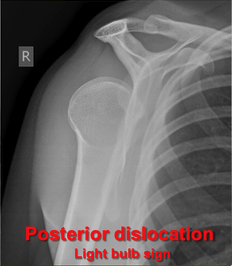

What is shown on this X-ray?